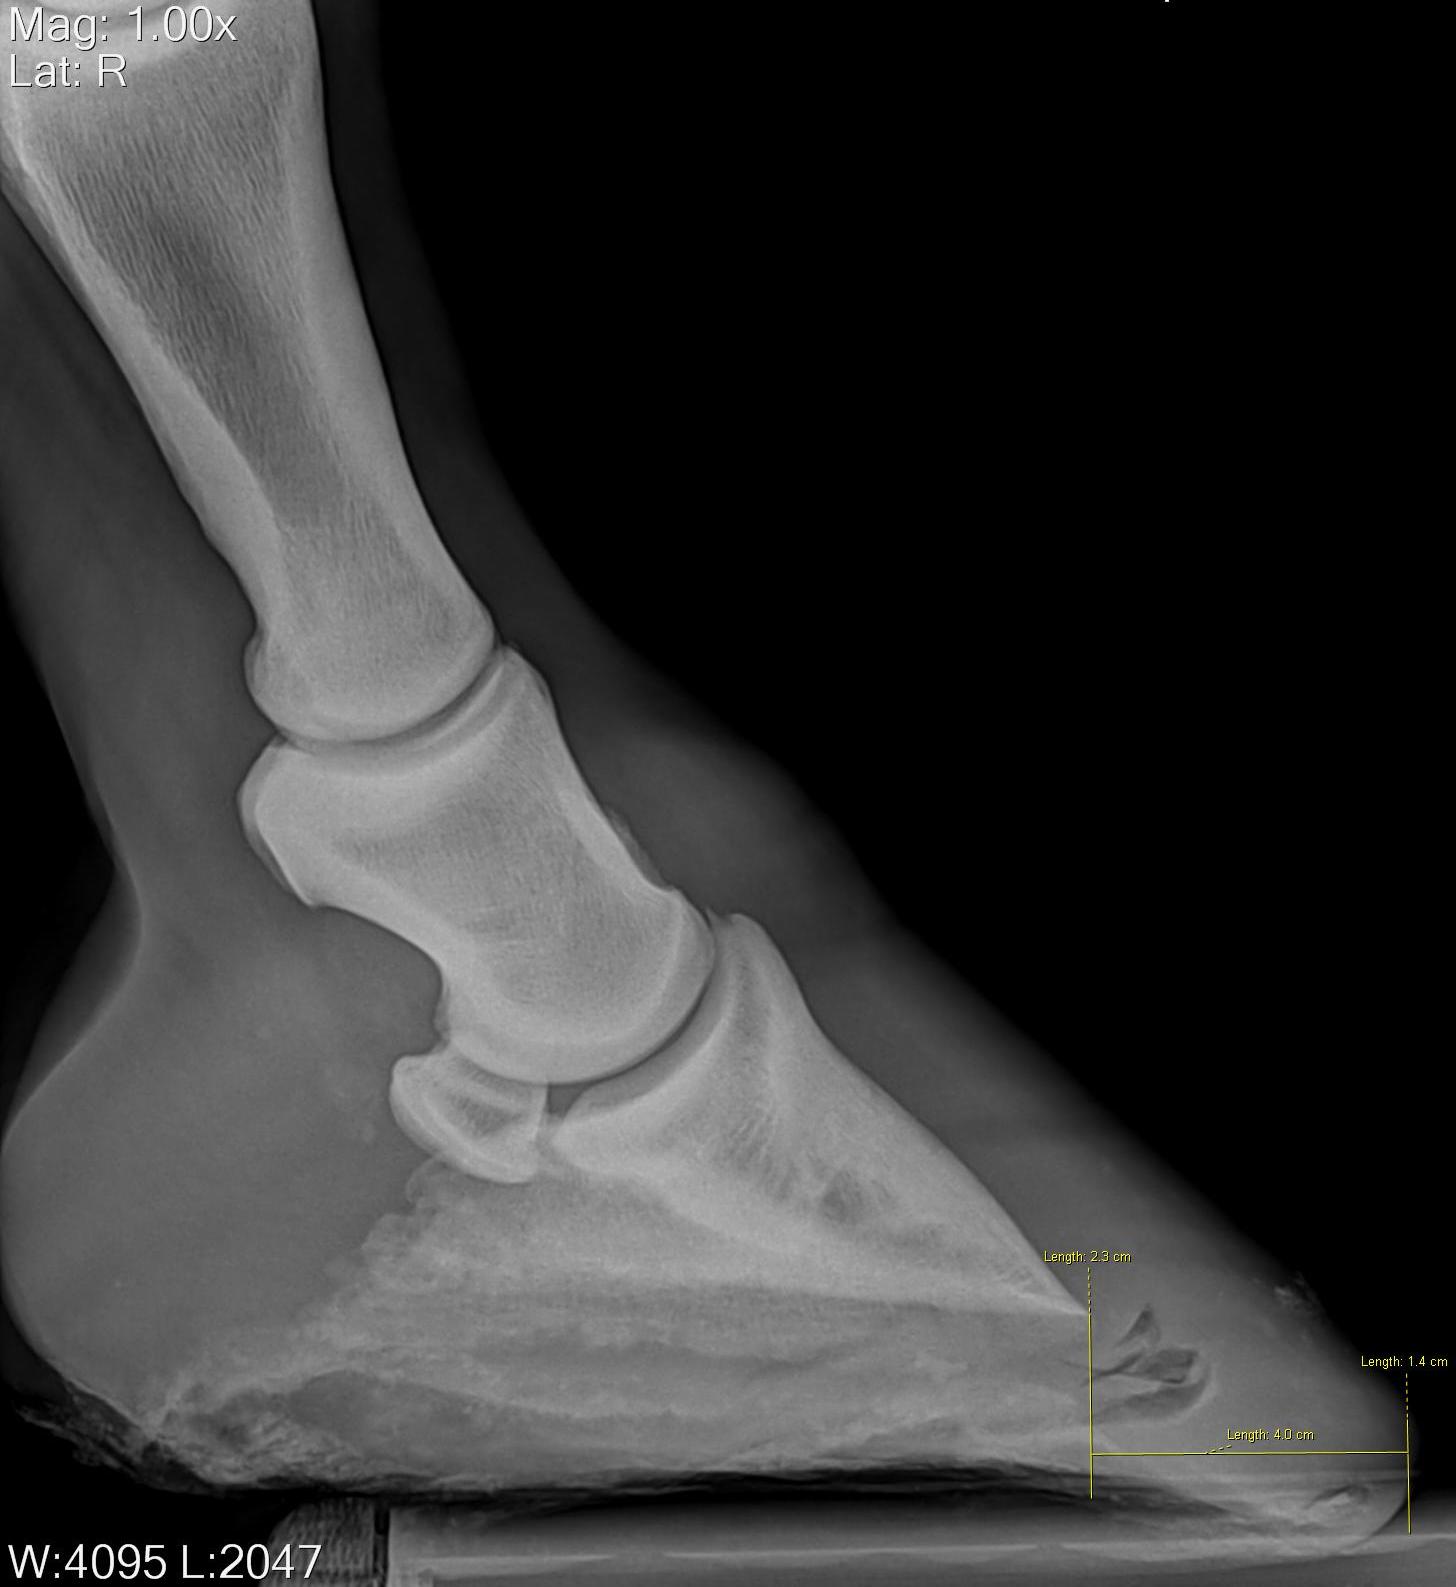

X ray horse

X ray horse 133 фото